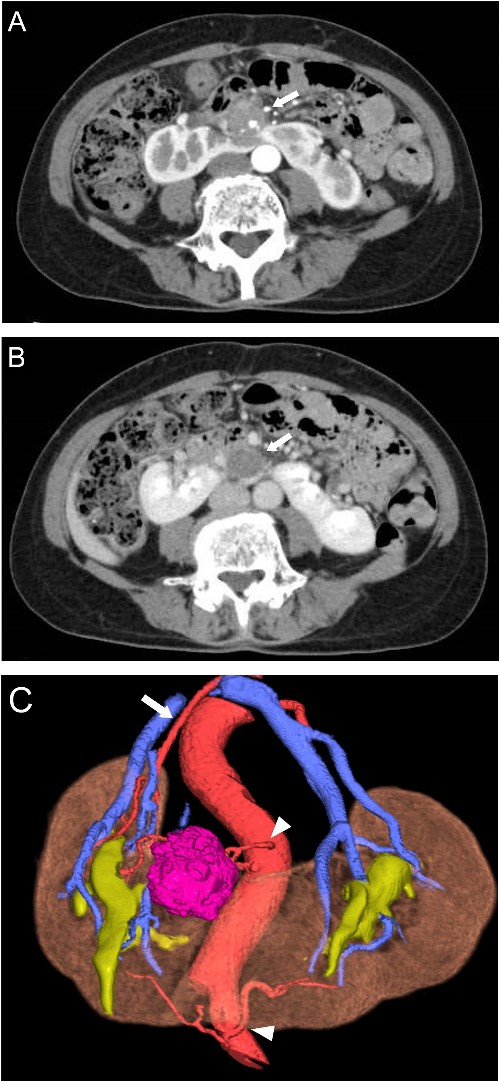

A 65-year-old woman presented to our department with an incidental 27 mm renal tumor in the isthmus of horseshoe kidney. Contrast-enhanced computed tomography (CT) imaging revealed that this tumor displayed slight enhancement with a solid component, accompanied by cystic and calcified elements (Fig. 1A and B). Based on these findings, we clinically diagnosed the renal cell carcinoma cT1aN0M0. Further assessment via three-dimensional (3D) CT revealed a single artery arising from the aorta to the right kidney, along with two arteries supplying the cephalic and caudal sides of the isthmus from the aorta and iliac artery, respectively (Fig. 1C).

Preoperative CT scans. (A) Contrast-enhanced CT showed heterogeneous enhancement of the tumor in the arterial phases (arrow). (B) The cystic area of the tumor had no enhancement in the venous phase (arrow). (C) 3D-CT demonstrated one artery arising from the aorta to the right kidney (arrow) and two arteries supplying the isthmus and tumor arising from the ventral side of the aorta and left common iliac artery (arrowhead).